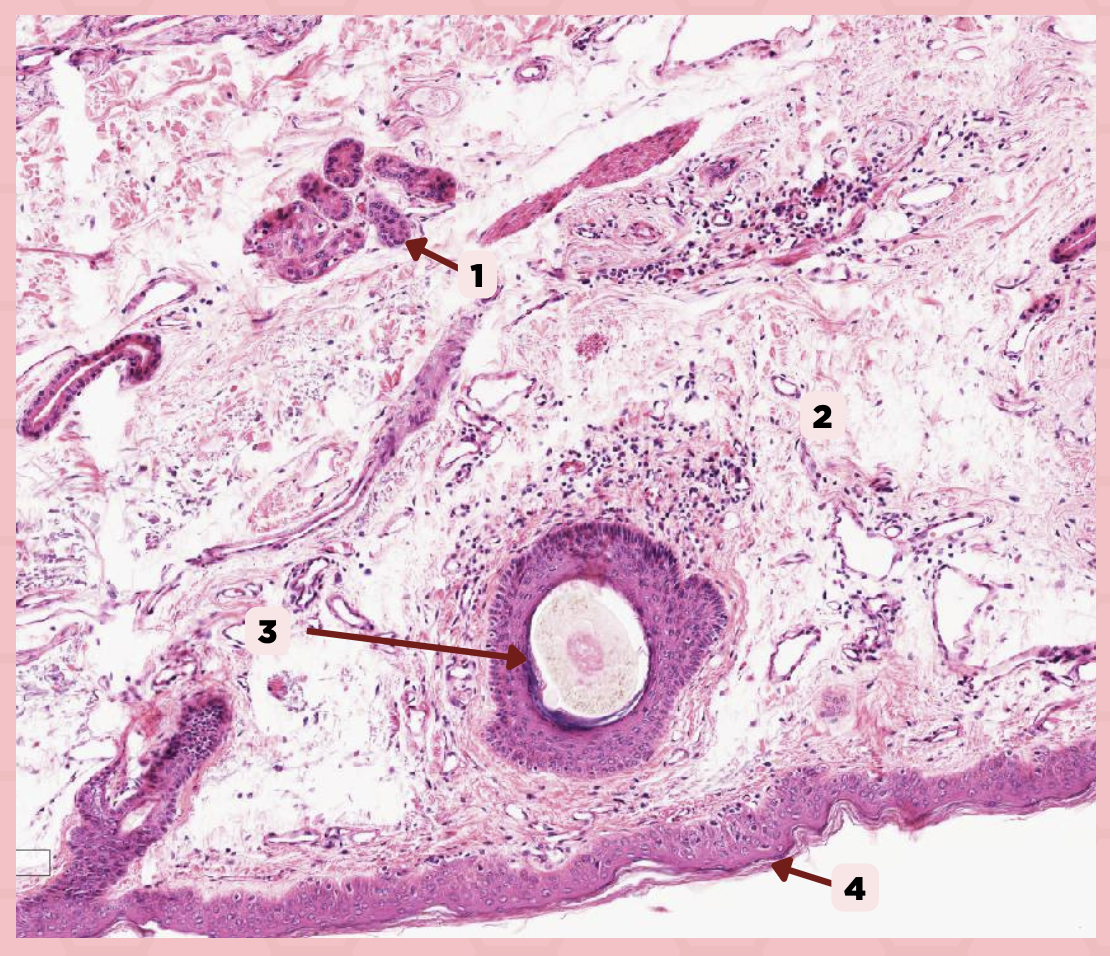

Lip

What specimen is being showed in the picture?

Epidermis

Identify the structure labeled as 1.

Dermis

Identify the structure labeled as 2.

Arrector Pilli Muscle

Identify the structure labeled as 3.

Hair Follicle

Identify the structure labeled as 4.

Sebaceous Glands

Identify the structure labeled as 5.

Lip

What is the specimen showed in the picture?

Epidermis

Identify the structure labeled as 1.

Dermis

Identify the structure labeled as 2.

Arrector Pilli Muscle

Identify the structure labeled as 3.

Hair Follicle

Identify the structure labeled as 4.

Sebaceous Glands

Identify the structure labeled as 5.